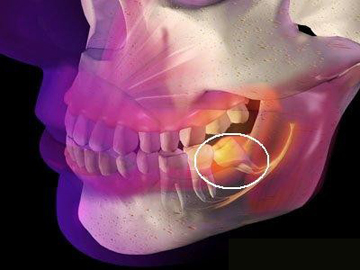

1、智齒位置:智齒的位置是影響拔除費用的重要因素之一,智齒的位置越深,手術難度越大,拔除費用也就越高。

2、手術復雜性:拔智齒手術的復雜性也會影響費用,如果智齒生長位置正常,手術相對簡單;如果智齒被埋在骨頭里,需要切開牙齦和骨頭,手術難度增大,費用相應增加。